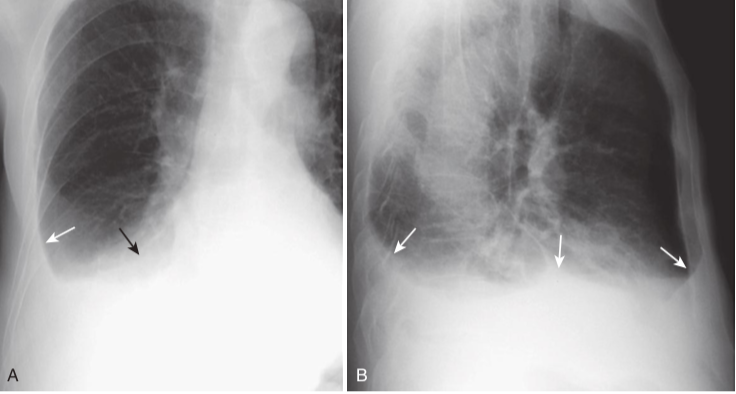

Normal versus laminar pleural effusion.

A, A normal patient in whom the normally aerated lung extends to the inner margin of each of the ribs (white arrows). The costophrenic sulcus is sharp (black arrow). B, There is a thin band of increased density that extends superiorly from the lung base (white arrow) but does not appear to cause blunting of the costophrenic angle (black arrow). This is the appearance of a laminar pleural effusion, which is most often associated with either congestive heart failure or lymphangitic spread of malignancy in the lung. This patient was in congestive heart failure.